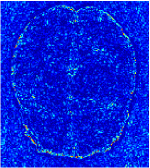

In general supervised learning, training data need to be in the same or similar distribution, heterogeneous data exhibits different structure variations of features which hinders CNNs to extract features efficiently. In our experiments, raw measurements sampled from different ratios of compressed sensing display different levels of incompleteness, these undersampled measurements do not fall in the same distribution but they are related. Different sampling masks are shown at the bottom of Figure 1 and 2 may have complemented sampled points, in the sense that some of the points which sampling ratio mask does not sample have been captured by other masks. In our experiment, different sampling masks provide their own information from their sampled points so that four reconstruction tasks help each other to achieve an efficient performance. Therefore, it explains the reason that Meta-learning is still superior to conventional learning when the sampling ratio is large.

In this section, we test the generalizability of the proposed model that tests on unseen tasks. We fix the well-trained task-invariant parameter and only train for sampling ratios 15%, 25% and 35% with radio masks and sampling ratios 10%, 20%, 30% and 40% with Cartesian masks. In this experiment, we only used 100 training data for each CS ratio and apply a total of 50 epochs. The averaged evaluation values and standard deviations are listed in Table 5.4 and 5.4 for reconstructed T1 and T2 brain images respectively that proceed with radio masks, and Table 5.4 shows the qualitative performance for reconstructed T2 brain image that applied random Cartesian sampling masks. In T1 image reconstruction results, meta-learning improved 1.6921 dB in PSNR for 15% CS ratio, 1.6608 dB for 25% CS ratio, and 0.5764 dB for 35% comparing to the conventional method, which in the tendency that the level of reconstruction quality for lower CS ratios improved more than higher CS ratios. A similar trend happens in T2 reconstruction results with different sampling masks. The qualitative comparisons are illustrated in Figure 2, 4 and 5 for T1 and T2 images tested in skewed CS ratios in radio masks, and T2 images tested in Cartesian masks with regular CS ratios respectively. In the experiments that conducted with radio masks, meta-learning is superior to conventional learning especially at CS ratio 15%, one can observe that the detailed region in red boxes keeps edges and is more close to the true image, while conventional method reconstructions are hazier and lost details in some complicated tissue. The point-wise error map also indicates that Meta-learning has the ability to suppress noises.